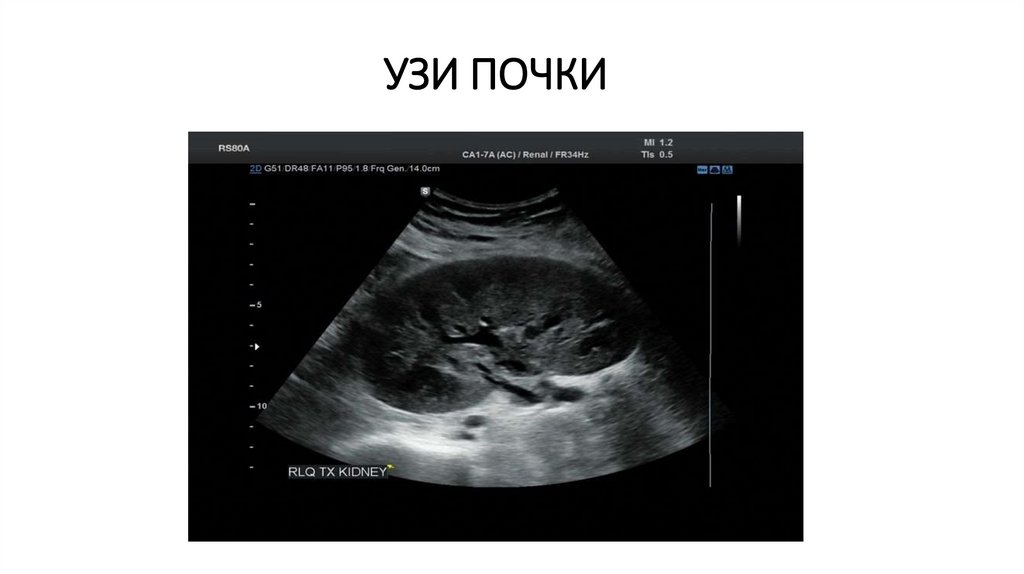

УЗИ ПОЧКИ

15. УЗИ ПОЧКИ

Органы забрюшинного пространства: почки и мочеточники, надпочечники, лимфатические узлы